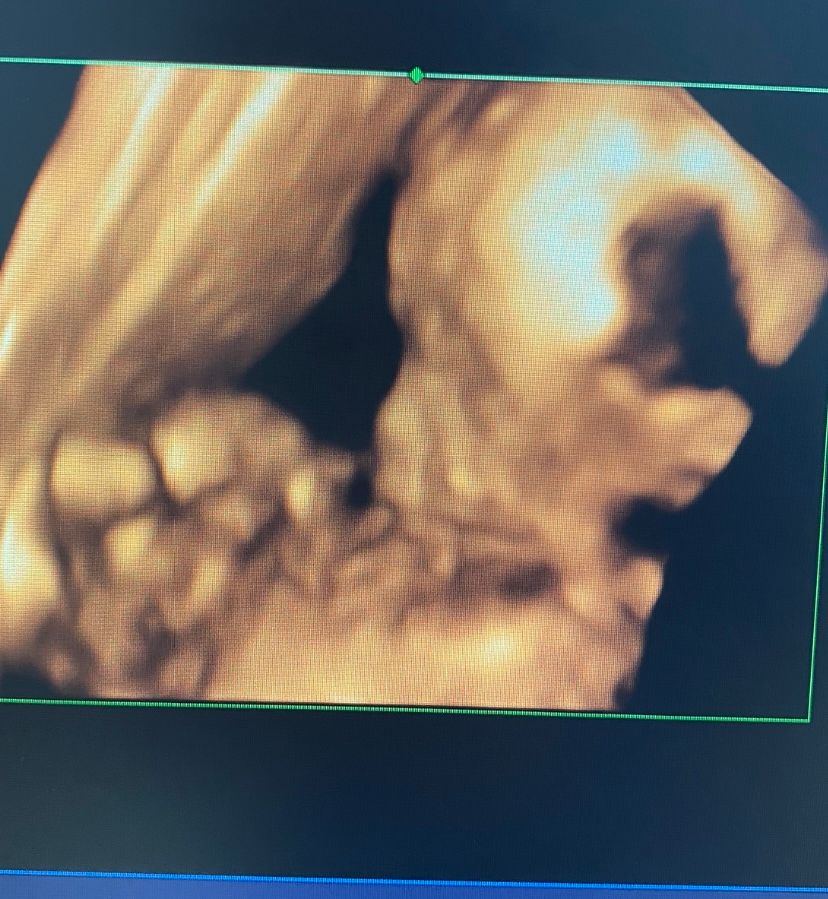

🐣💕Птенчик мой на 4д узи

Девочка моя маленькая😍🙏🏼пальчик сосет малышка

😀А потом возникают вопросики, откуда же такая страсть к сосанию пальчика)))))).